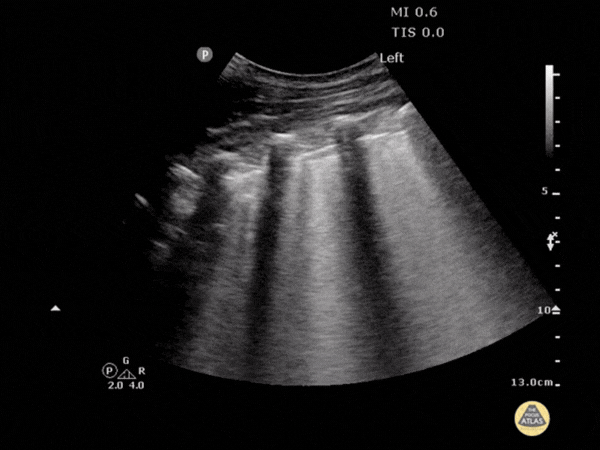

Vérifier si les voies urinaires hautes sont obstruées (colique néphrétique).

Points clés :

- Repérage des loges rénales en coupes longitudinale et transversale.

- Différenciation entre le sinus rénal hyperéchogène et le parenchyme.

- Identification de l'anéchogénéité des calices et du bassinet dilatés.

- Comparaison systématique avec le rein controlatéral.

- Mise en garde face aux pièges : pelvis extrarénal ou kystes parapelviens (diagnostics différentiels).